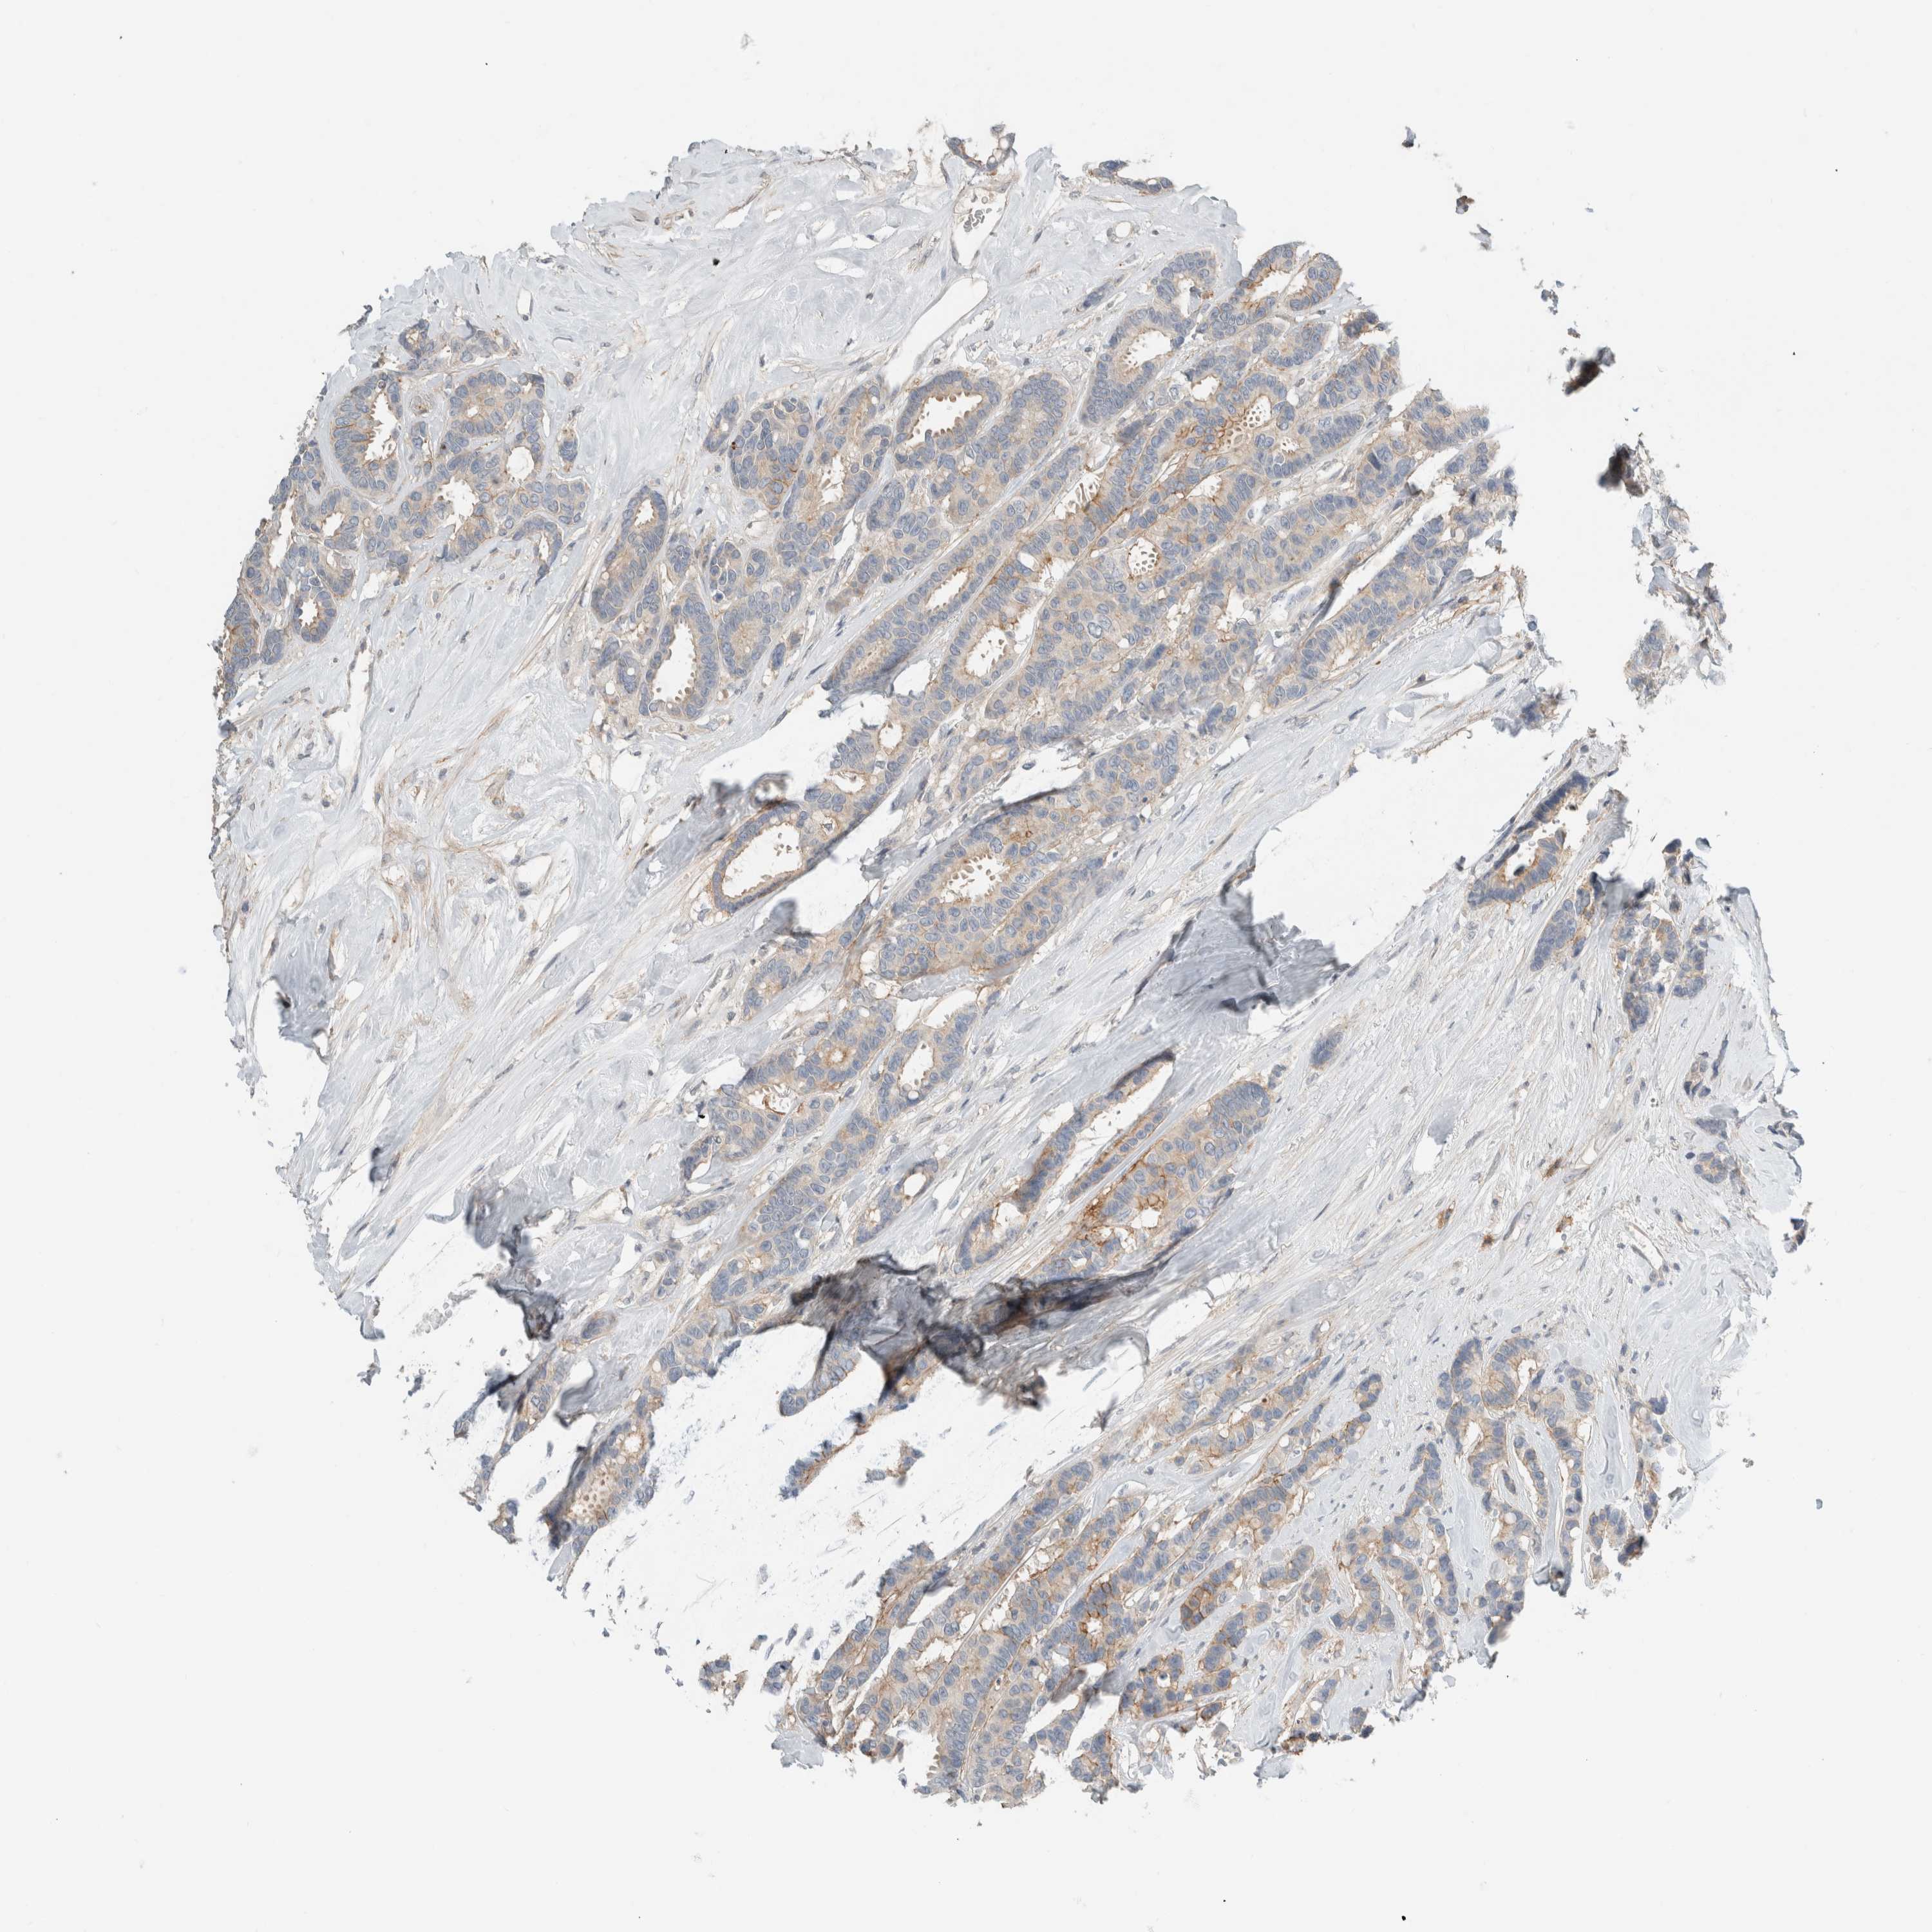

BRCA TCGA BRCA VALIDATION PROTEIN EXPRESSION

ANTIBODIES

AND

VALIDATION